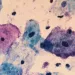

O critério ou escore de Nugent avalia a saúde do microbioma através da microscopia, calculando uma pontuação baseada na abundância de morfotipos bacterianos associados a uma microbiota "saudável" ou associados à vaginose bacteriana (VB). Entretanto, os CSTs classificam os microbiomas vaginais em cinco tipos com base na dominância bacteriana, indicando estados "eubióticos" dominados por Lactobacillus ou estados diversos e pobres em Lactobacillus associados à disbiose.